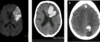

label angiogram

2 main types of stroke? how do u know what type it is?

u wont know, cuz they present the same way!

until u get a CT scan